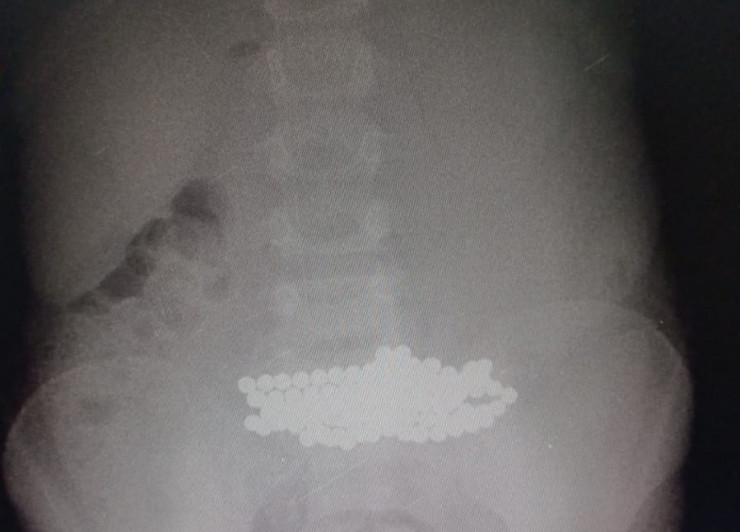

"На прошлой неделе провели операцию девочке, которая поступила в больницу для прохождения магнитно-резонансной томографии (МРТ). Во время осмотра в носу ребенка врачи обнаружили магниты, уже с перфорацией перегородки носа. После чего ребенок был направлен на рентген-исследование, которое выявило огромное скопление магнитов в желудке. В итоге мы вытащили более 100 мелких магнитов", - говорит Ринат Байгиреев.